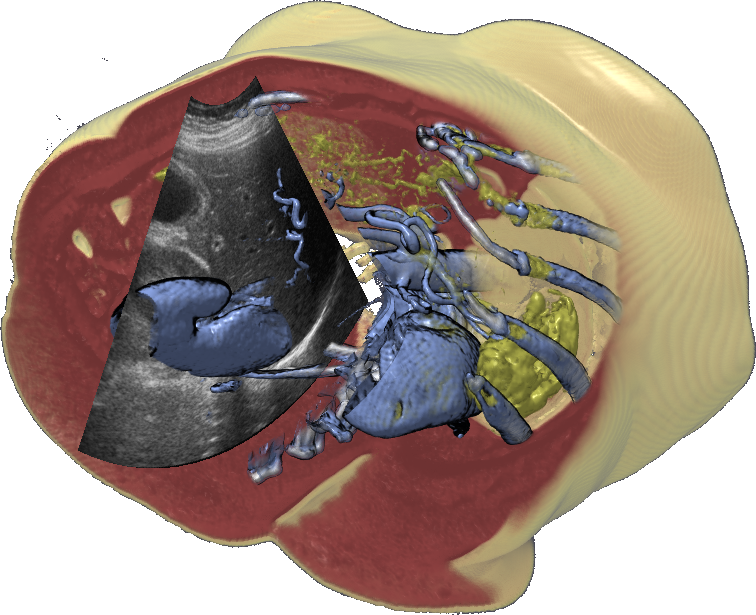

Burns et al. applied illustrative cut-aways combined with 3D freehand ultrasound burns07 . This provide a better spatial overview for the ultrasound images. To add more information onto the 2D ultrasound image, Viola et al. proposed an approach to enhance the ultrasound image by overlaying higher order semanticsviola08 , in this case in the form of Couinaud segmentation. The segmentation is pre-defined in a CT dataset and visually verified using exploded views. To combine it with ultrasound images, CT dataset is co-registered with the ultrasound using rigid transformation according to user defined landmarks. The different segments are superimposed onto the ultrasound image enabling the user to directly see which segments are in the visible. To improve ultrasound video analysis, Angelelli et al. used a degree-of-interest (DOI) function superimposed on the image angelelli10 . The video sequence was presented as a graph, where the height was defined by the amount the current ultrasound image covered the DOI-function.